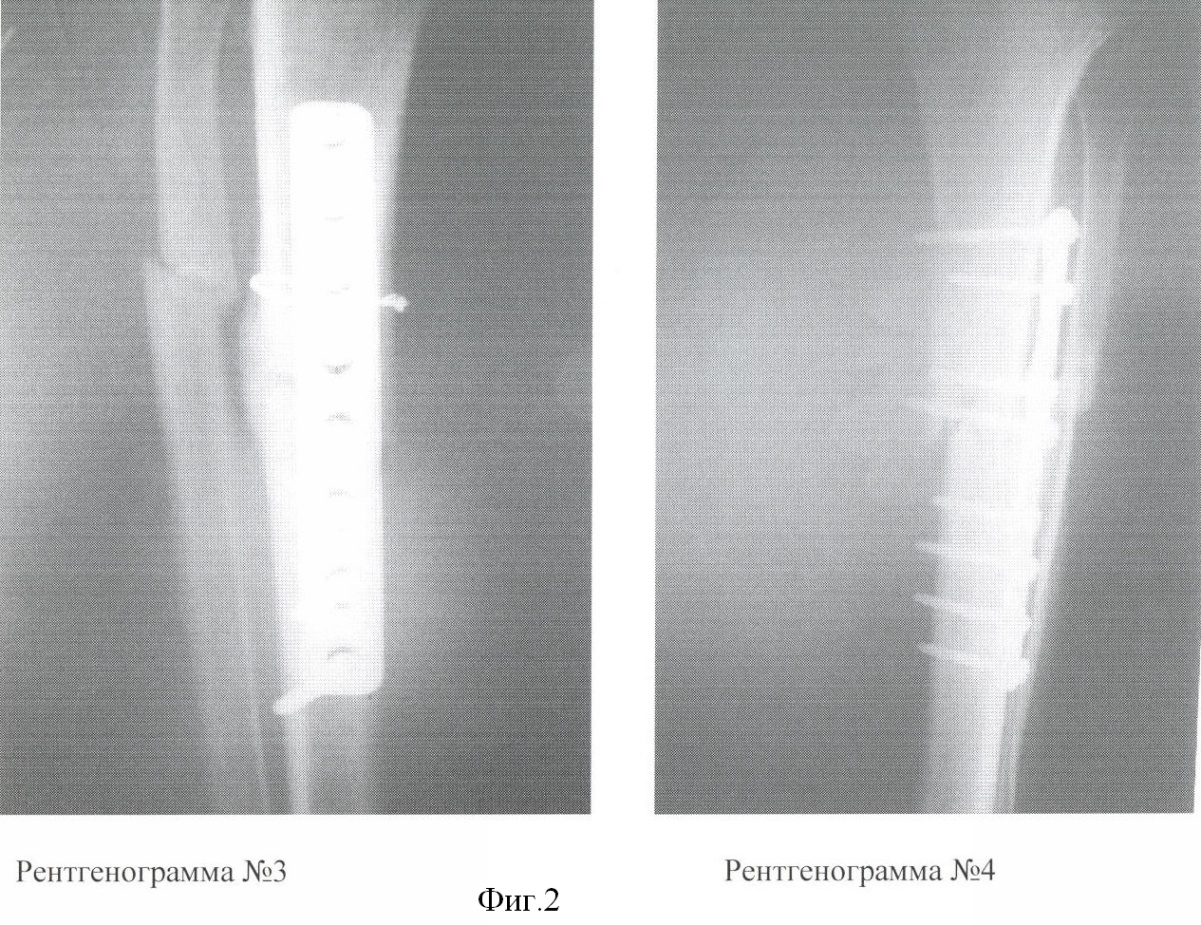

Данные лечения представлены на фиг.1 Рентгенограмма 1 – с применением АМСК. Оскольчатый перелом обеих костей в/3 голени со смещением, 8 недель после операции (интрамедуллярный металлоостеосинтез большеберцовой кости). На снимке видна выраженная периостальная мозоль в зоне имплантации АМСК и интермедиальная мозоль, сращение оскольчатого перелома в/3 малоберцовой кости. Рентгенограмма 2 – лечение аналогичной травмы без применения АМСК. Оскольчатый перелом обеих костей в/3 голени со смещением, 8 недель после операции (интрамедуллярный МОС б/берцовой кости с дополнительной фиксацией осколков проволочным серкляжем). На снимке отсутствуют отчетливые признаки сращения, щель между отломками не заполнена костной тканью, начальные признаки интермедиальной мозоли. Отсутствуют признаки сращения м/берцовой кости.

При выписке больному (лечение с АМСК) были даны стандартные рекомендации после подобных операций. Через 8 недель после операции был выполнен рентгеноконтроль правой голени. На рентгенограмме (фиг.1, 1) отмечались выраженная периостальная мозоль в зоне имплантации АМСК и интермедиальная мозоль, сращение оскольчатого перелома в/3 малоберцовой кости.